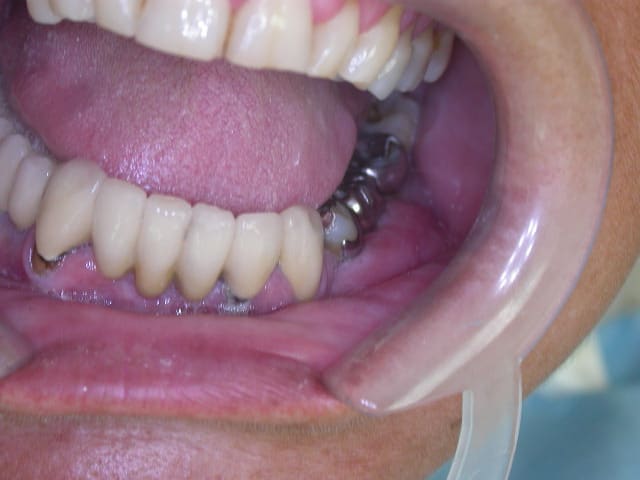

Faut lui dire de changer sa méthode de brossage...Elle a de superbes mylolyses (ou régler le problème de bruxisme si bruxisme il y a ). :))

Non pas de bruxisme, juste un brossage horizontal très certainement. Mais franchement ça n'est pas le plus grave dans sa cavité buccale.